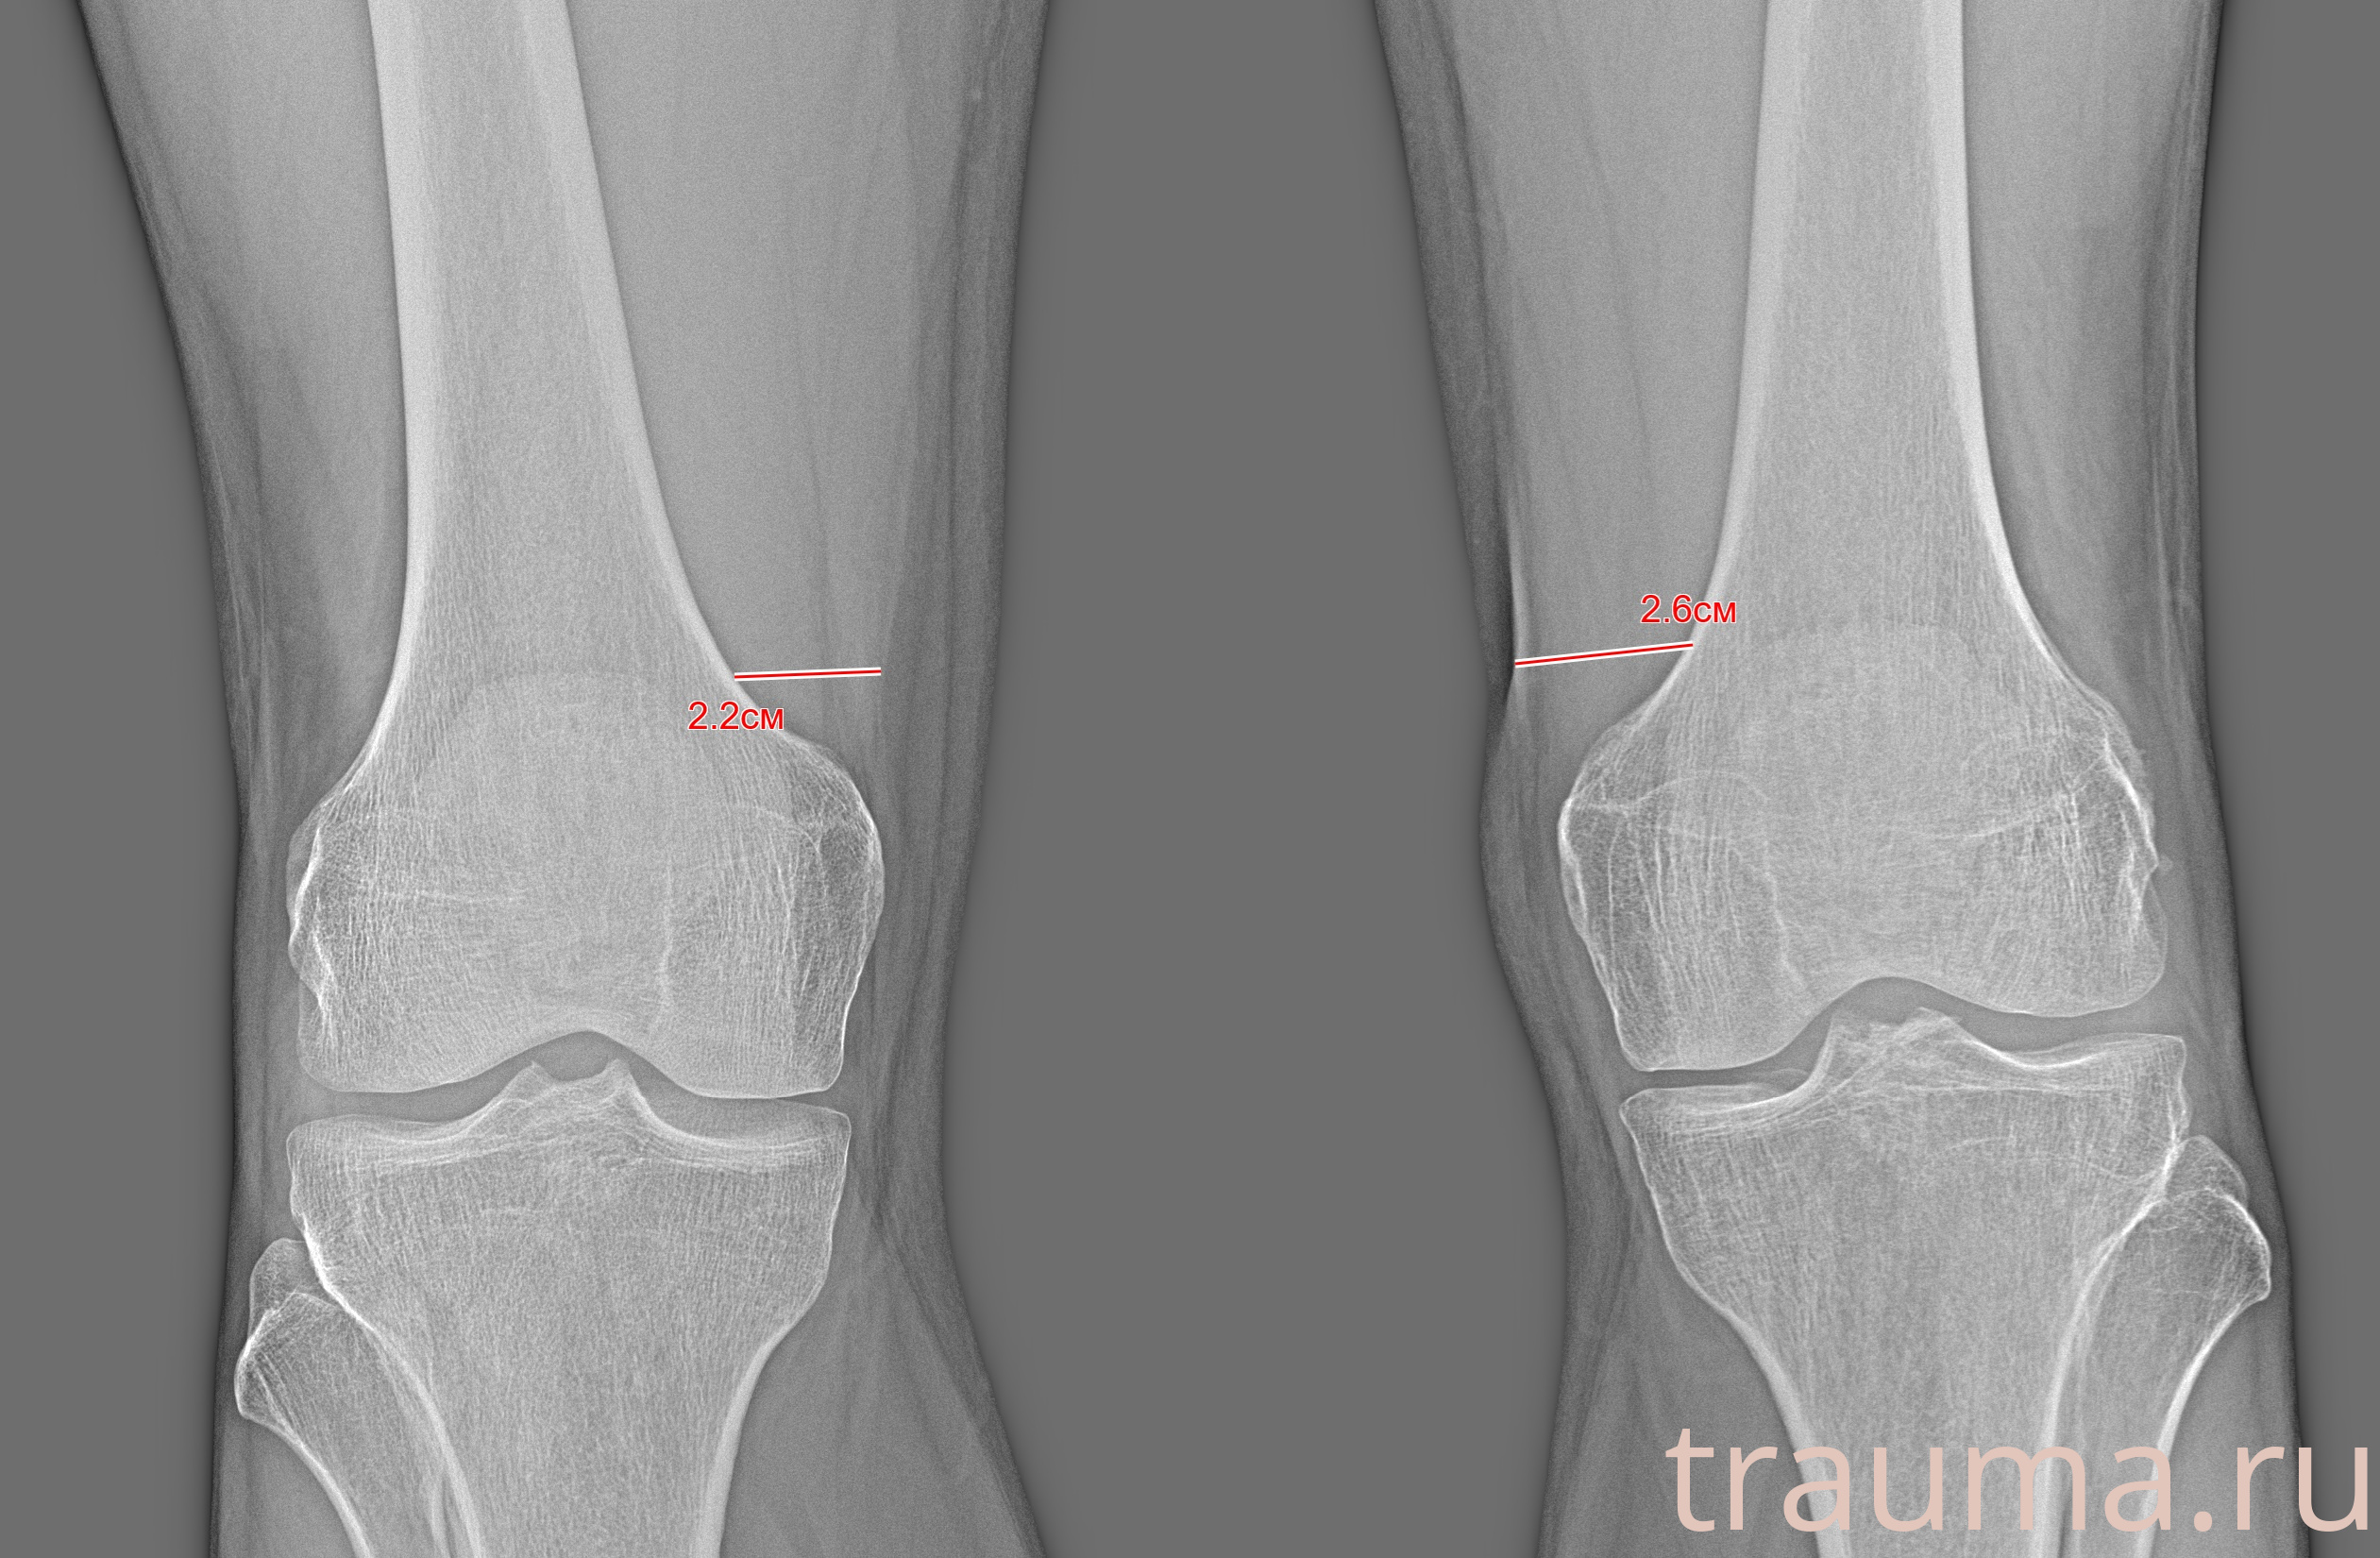

Рентген на дому: по вашему адресу приезжает врач-рентгенолог, травматолог-ортопед с мобильным рентгеновским аппаратом, проводит диагностику травмы или заболевания, делает необходимые рентгенограммы, дает рекомендации по дальнейшему лечению. Получить качественные снимки в домашних условиях возможно благодаря уникальной методике, разработанной МосРентген Центром для института  Склифосовского